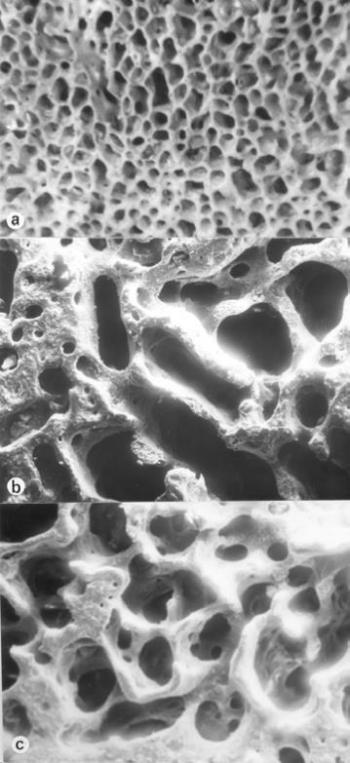

A poroticus hyperostosis (szinonimák: cribra orbitalia, cribra cranii, hyperostosis spongiosa, hyperostosis porotica, osteoporosis cranii) elsősorban a koponya, (főként a szemüreg) elváltozása (122. ábra) ám megjelenhet valamennyi lapos és csöves csonton. Mikroszkópos képével Hamperl és Weiss (1955), Marcsik és Kósa (1976), az elektronmikroszkópos és hisztomorfometriai eltérésekkel Józsa és Pap (1991) foglalkoztak. Morfológiai képe a folyamat súlyossága szerint eltérő. A poroticus típusban a corticalison tág nyílások keletkeznek (123. ábra), a spongiosus alakban a corticalis felszivódik, a felületet szívacsos állomány képezi (124. ábra), trabeculáris formában a diploe gerendái a környező csont szintje fölé burjánzanak (125. ábra) ami a rtg-felvételen „kefekoponya” alakjában jelentkezik (126. ábra). Mikroszkóposan a spongiosa gerendáinak feldúsulása, a gerendákon másodlagos üregek kialakulása állapítható meg (Józsa és Pap 1991), az egységnyi ürtartalomban megnő a csontvelőt hordozó felület, az újonnan képződő gerendák kóros szerkezetüek (123. ábra, 124. ábra, 125. ábra). Fokozott vörösvértest produkcióval járó valamennyi kórképben megjelenhet, vashiányos vérszegénységben 60-90%, Cooley anemiában 100%, sarlósejtes anaemiában 50-60%, maláriásokon 40-60%, cyanoticus szívfejlődési rendellenességekben 1-5% gyakoriságú (15. táblázat).

123. ábra. a) A poroticus terület sztereomikroszkópos képe 20× nagyítás b) Ugyanezen rész elektronmikroszkópos képe. SEM 500× nagyítás

124. ábra. a) A spongiosus elváltozás sztereomikroszkópos képe. 20× nagyítás b)–c) A trabeculák között változó nagyságú üregek, a csontvelőt hordozó csontfelület jelentősen megnövekedett. SEM b) 600×, c) 1000× nagyítás

125. ábra. a) A trabecularis formában a csontgerendák (T) a lamina externa szintje (LE) fölé emelkednek. SEM 170× nagyítás b) A kóros szerkezetű trabecula kinagyított képe SEM 1200× nagyítás